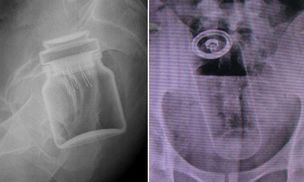

Poszli z tym do lekarza. Niewiarygodne, jak się tłumaczyli